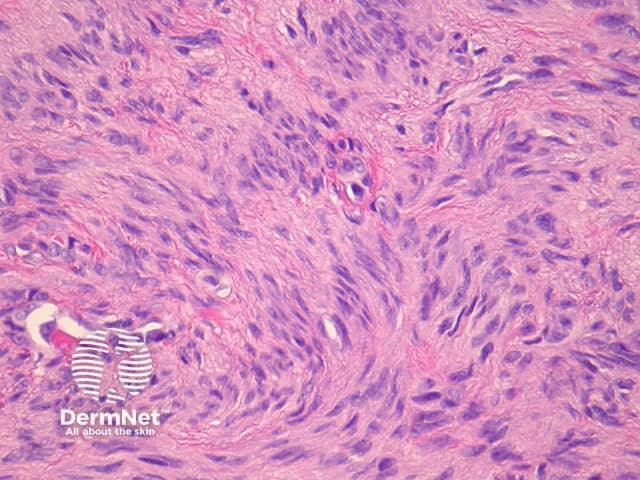

Sections through epithelioid dermatofibroma show a centrally located, circumscribed tumour underlying an epidermal collarette. The tumour is composed of cells arranged in sheets and sometimes a storiform pattern. Individual cells show epithelioid morphology with abundant eosinophilic cytoplasm with round vesicular nuclei and prominent nucleoli (figures 5, 6). The cells may be markedly enlarged and display some nuclear atypia and mitoses. There is frequently an associated inflammatory cell infiltrate which can be helpful for the diagnosis.